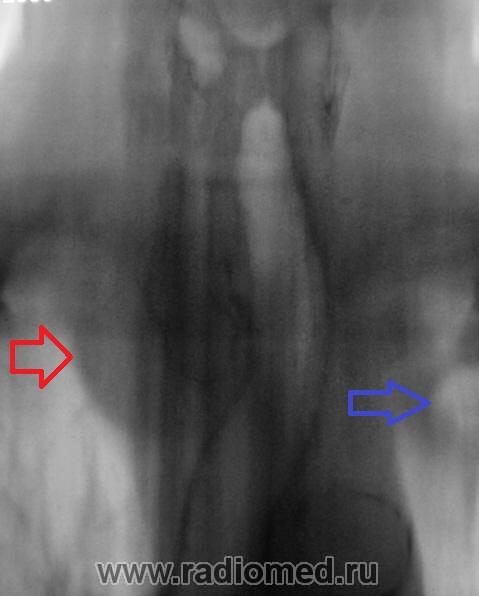

Синяя стрелка, как понимаю "кругляк", который смущает Валентина Львовича? К сожалению край изображения, тяжело что-то понять. Вероятнее всего это 1 ребро.

Зато Красная стрелка - явно зоб

При "клике" на то, что помечено красной стрелкой, дифференцируются известковые включения?